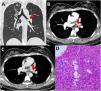

Lymphoepithelioma-Like Carcinoma Presents as a Bronchial Nodule